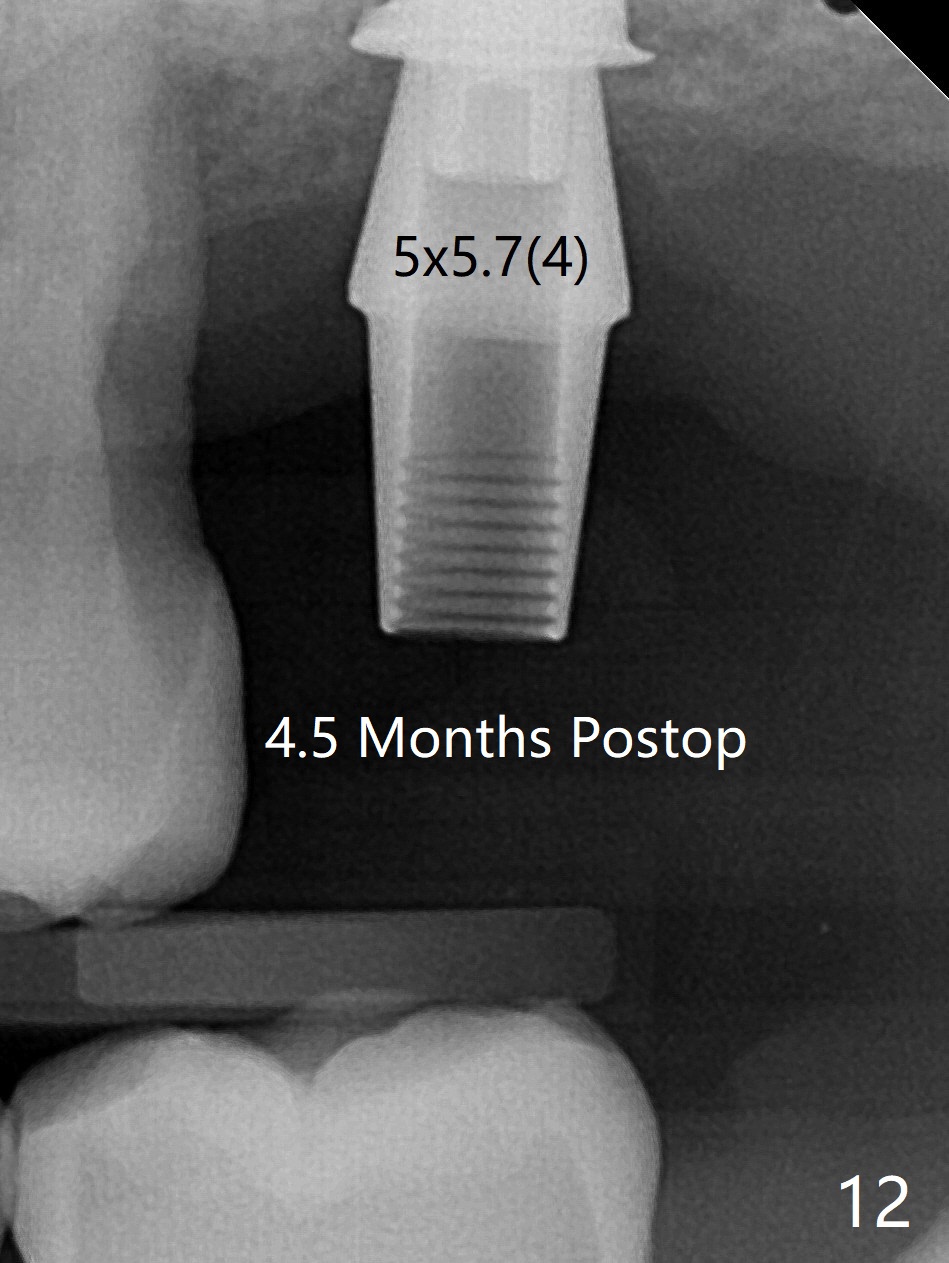

cartridge),植入短小植体(4.5x7毫米,原定(5x8.5毫米)图二),由于稳定性好,使用5.5毫米profile钻头后,放置5.5x4毫米愈合基台(图三)。术后病人没有什么上颌窦不适和分泌物。估计Novo

Bone在上颌窦里凝固了。其实左侧上颌窦粘膜术前增厚(图四,五:L),人工骨仿佛弥撒在上颌窦膜中(图六)。术后一周病人没有任何鼻窦症状。术后4.5月旋转愈合基台时,病人感到疼痛,终止取模(图七),两个月后复诊,做progressive loading。术后5.5月旋转愈合基台时,植体一起出来,但是上颌窦膜没有破,放置大一号植体(报废)扭力不够(图八),再大一号扭力可以(图九),放置愈合帽。由于邻牙长(图九:双箭头),牙周敷料逗留三周不掉(图十:P)。撤除后,伤口愈合正常。The